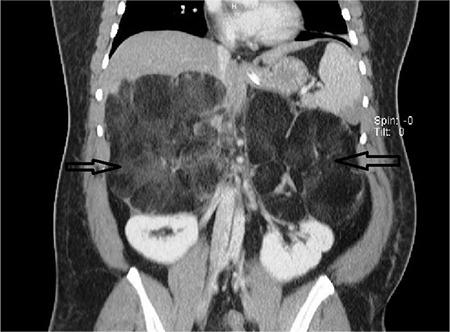

Giant Bilateral Adrenal Myelolipoma.

Balkan Med J. 2017 Sep 29;34(5):476-477. doi: 10.4274/balkanmedj.2016.1749.

Giant Bilateral Adrenal Myelolipoma.巨大双侧肾上腺髓脂肪瘤